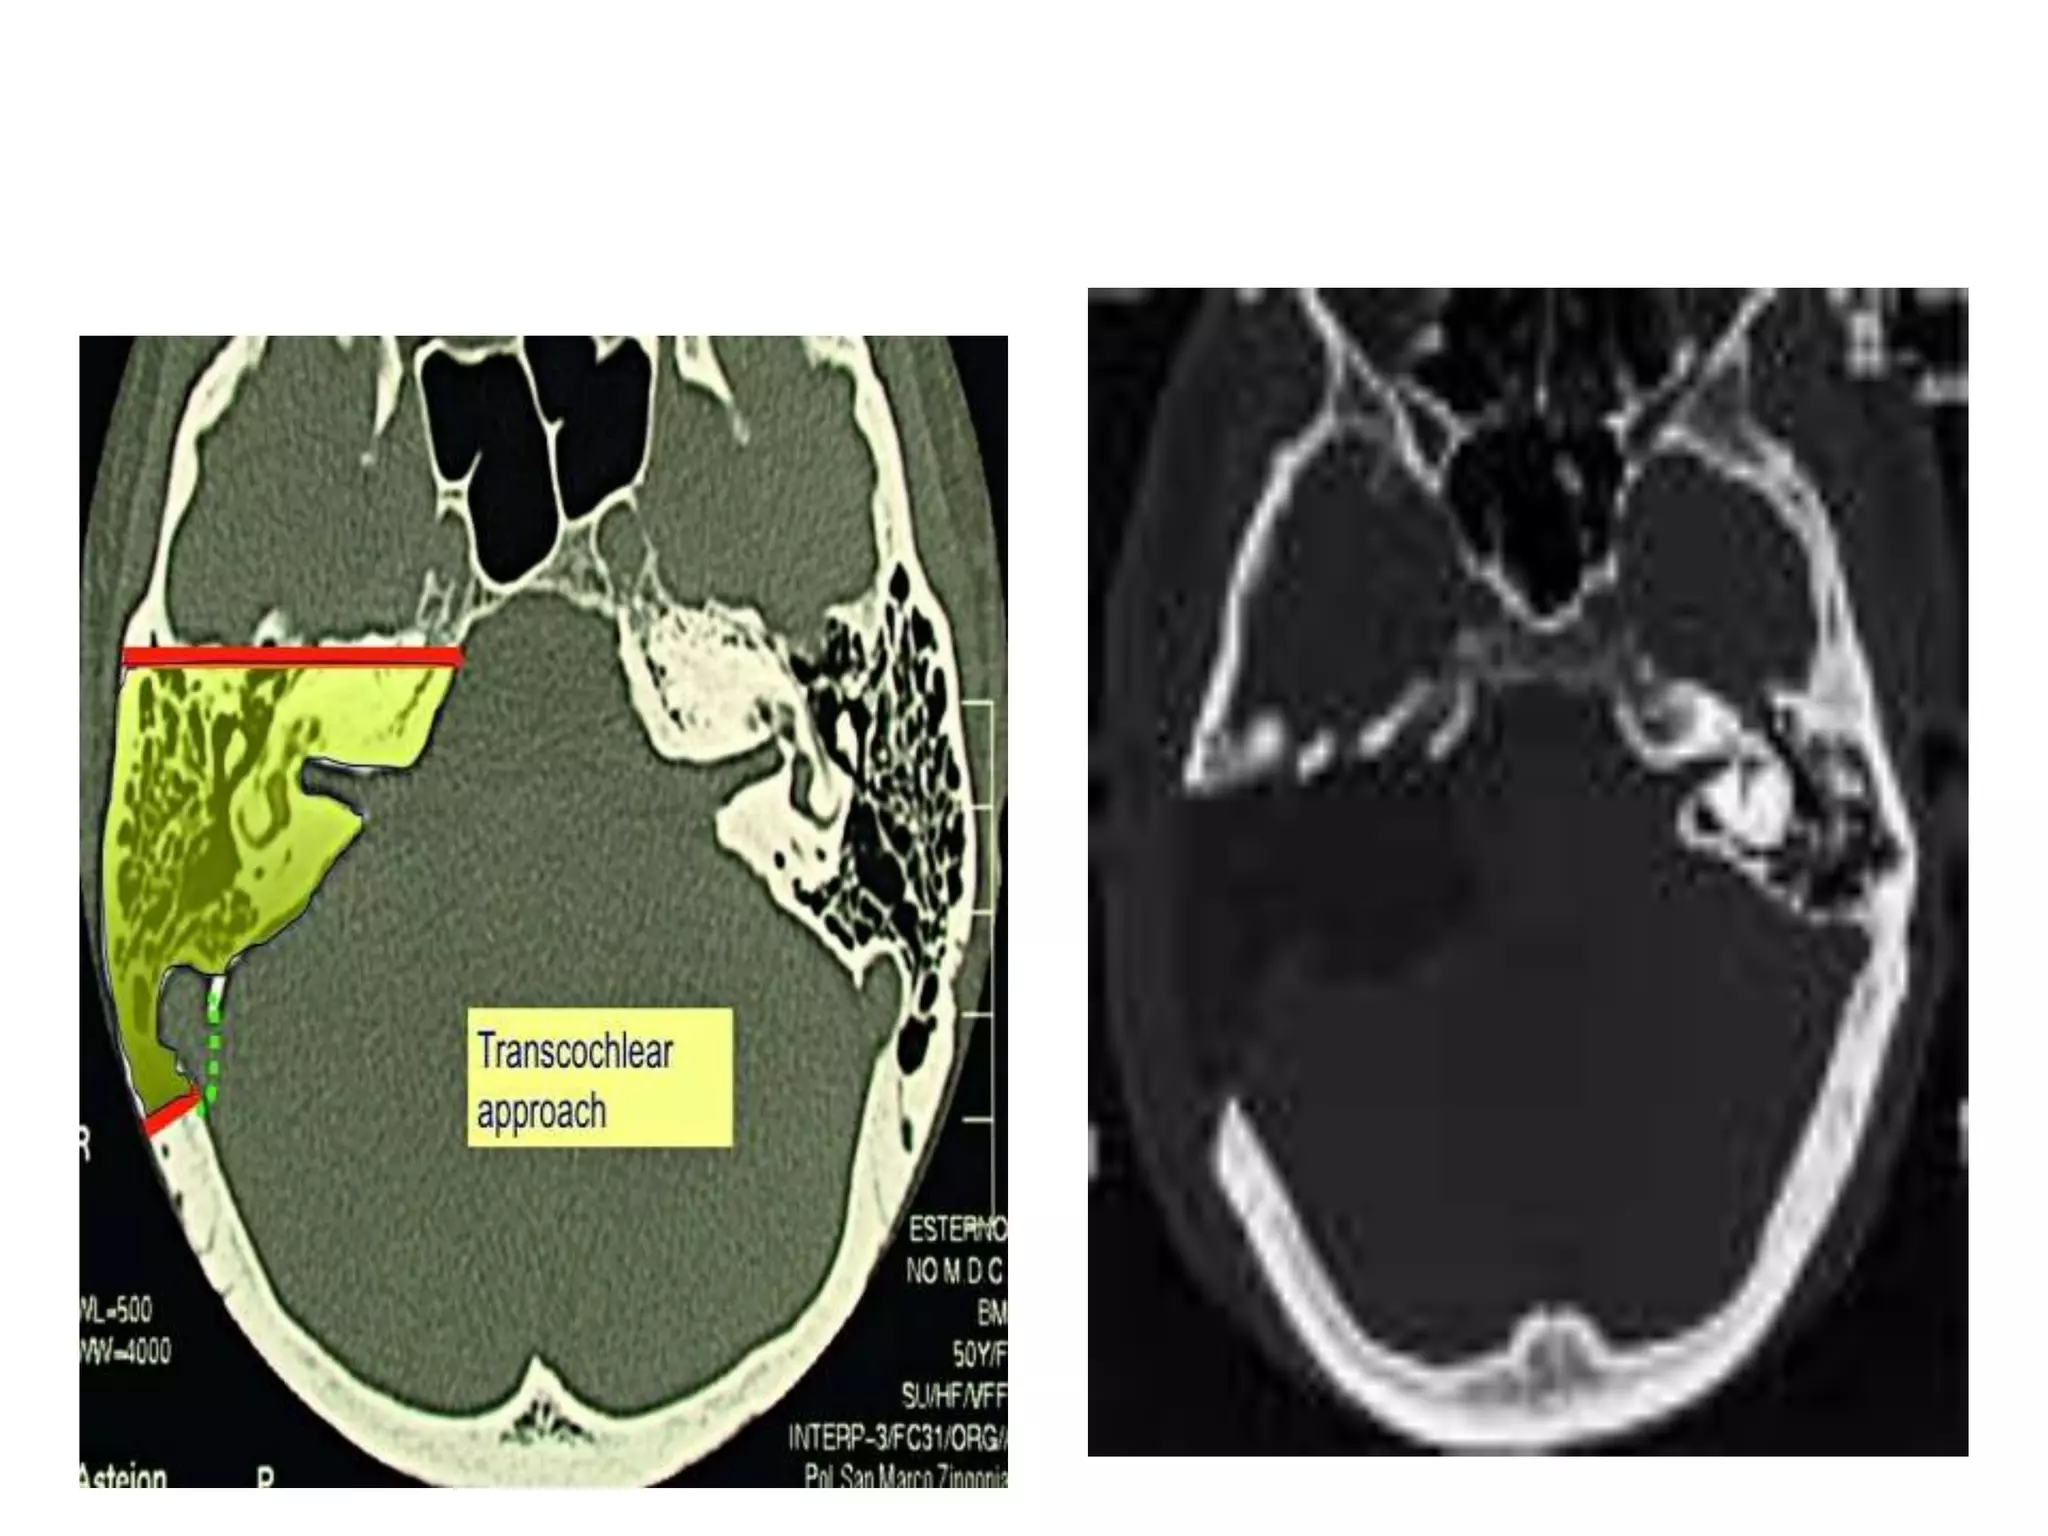

• Transcochlear approach

• The transcochlear approach is an extension of the

translabyrinthine approach, with three main

additional steps: removal of outer ear canal and

tympanum and entire petrous bone up to the

clivus, posterior transposition of the facial nerve,

drilling of the cochlea and closure of the external

auditory canal

• The approach gives wide access to the CPA and is

suitable for large lesions with anterior extension

into the prepontine cistern. The cavity is filled

with fat. The approach is the widest

surgical corridor in the lateral skull base.

• The complete petrous bone is removed

including the external ear and middle ear

• The approach allows good exposure of the

complete CPA, with the surgical corridor

extending from the anterior wall of the

external ear canal to the clivus, making a

surgical cavity of the entire petrous bone